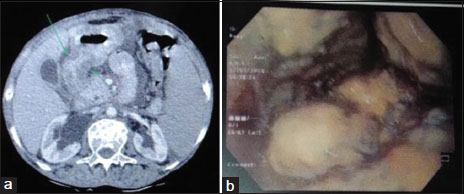

The patient was planned for surgery in view of gastric outlet obstruction and metabolically active lesion confined to the stomach only. She underwent subtotal gastrectomy [Figure 2]a with Roux-en-Y gastrojejunostomy. Histopathological examination (HPE) of the resected distal stomach revealed granulomatous inflammation with caseous necrosis, compatible with TB [Figure 2]b. Postoperative period was uneventful. She was discharged on postoperative day 15 on Category 1 antitubercular therapy (ATT). She has completed her ATT. The patient is under follow-up for the past 1½ years and asymptomatic till date [Figure 3]a and [Figure 3]b.

| Figure 2 Resected distal stomach with stenotic pylorus, (b) granulomatous inflammation with caseous necrosis

| Figure 3 Endoscopy and (b) contrast‑enhanced computerized tomography of the abdomen showing normal anastomosis with no evidence of recurrence in follow‑up